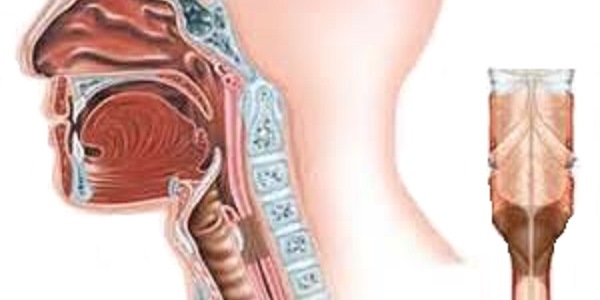

Стеноз гортани – сужение просвета гортани, вследствие которого человек не может нормально дышать. Если стеноз возникает на протяжении короткого времени и быстро проходит до начала явлений острой гипоксии в организме, значит это острый стеноз гортани.

Стеноз гортани представляет собой сужение дыхательных путей, что может привести к серьезным проблемам с дыханием. Врачи отмечают, что основными причинами возникновения этого заболевания являются аллергические реакции, инфекционные заболевания, травмы и опухоли. У детей стеноз часто связан с вирусными инфекциями, такими как круп, в то время как у взрослых он может быть следствием хронического воспаления или воздействия внешних факторов, таких как курение.